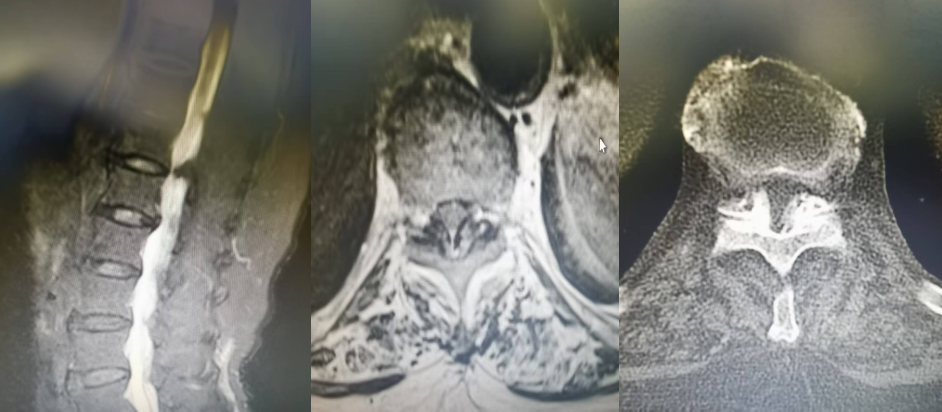

患者,女,82歲,T10/11黃韌帶鈣化并椎管狹窄,且伴有嚴(yán)重的骨質(zhì)疏松,術(shù)前雙下肢麻木、無力,不能正常行走。如果實(shí)施開放性手術(shù)需行全身麻醉下全椎板切除減壓內(nèi)固定治療,由于患者年齡大、耐受差,手術(shù)失敗率極高,經(jīng)過科室討論后決定給予微創(chuàng)手術(shù)治療。手術(shù)由郝清海副主任醫(yī)師主刀,在劉濤副主任醫(yī)師配合下順利完成UBE內(nèi)鏡下的黃韌帶鈣化物去除,椎管擴(kuò)大,脊髓減壓治療。手術(shù)切口約1.5cm,且能保留患者的運(yùn)動單元,術(shù)后患者無明顯腰背痛癥狀,神經(jīng)功能有極大恢復(fù),可自主下地行走,療效確切,患者及家人對手術(shù)效果非常滿意。

T10/11黃韌帶鈣化,椎管狹窄,硬膜囊受壓嚴(yán)重,腦脊液不通暢